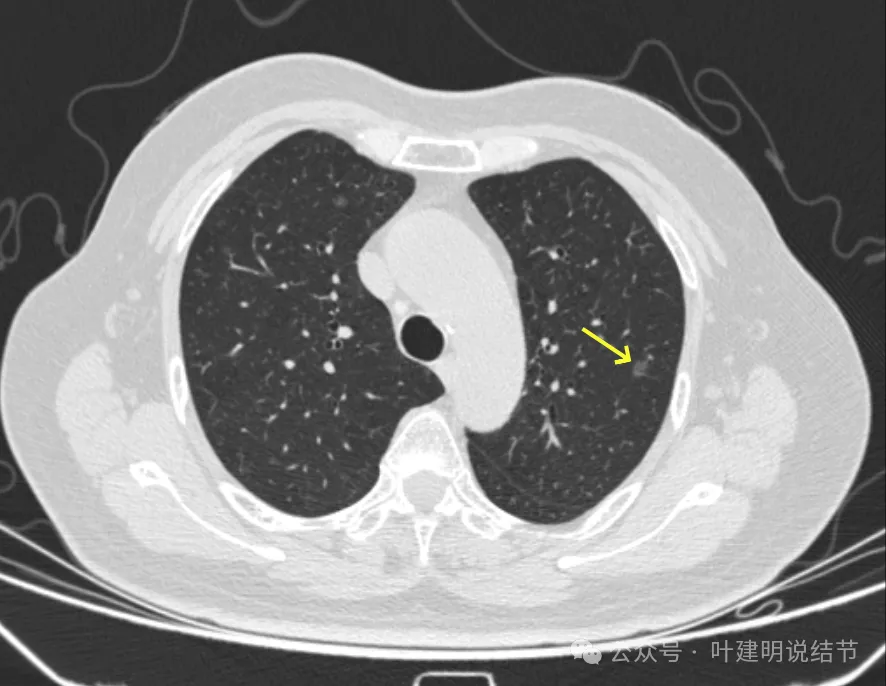

病灶38-39:左上叶与左下叶淡磨玻璃结节,轮廓较清,微小,轮廓较清。

病灶40:右叶边缘稍糊的磨玻璃结节,轮廓较清。

病灶44:右下叶磨玻璃结节,轮廓较清。

病灶45:左下叶磨玻璃结节,轮廓较清。

病灶46:左下叶磨玻璃结节,轮廓较清,密度稍高,贴着胸膜,轮廓与边界清。

病灶47:右下叶淡磨玻璃结节,轮廓较清。

病灶48:左下叶淡磨玻璃结节,轮廓较清,似有小血管征与小空泡征。